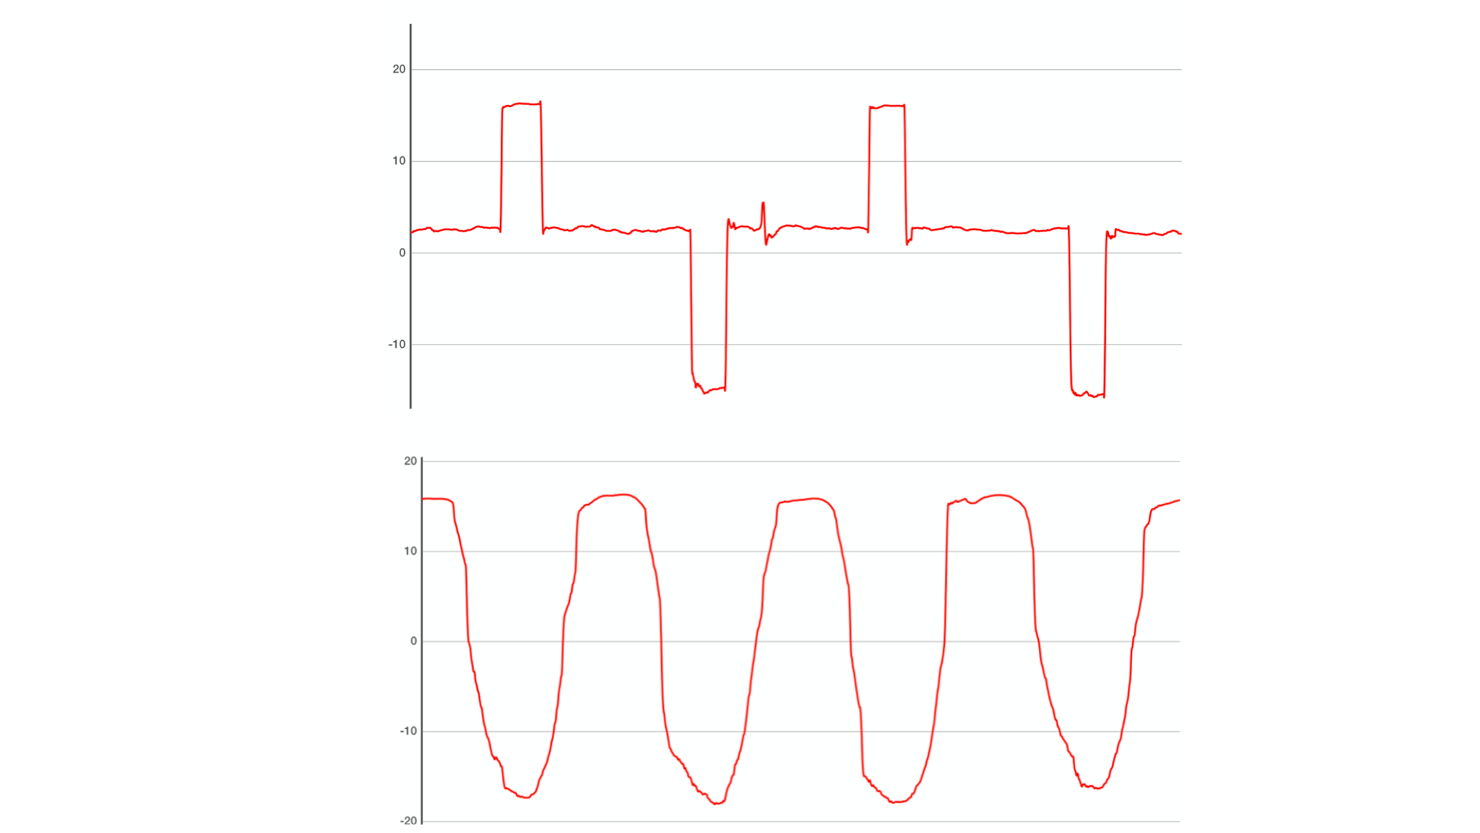

Perform an eye tracking exam in a few minutes just with an iPad.

We tested eVOG on a sample of patients and demonstrated it was able to distinguish reliably patients with eye movement abnormalities in comparison to the gold standard examination.